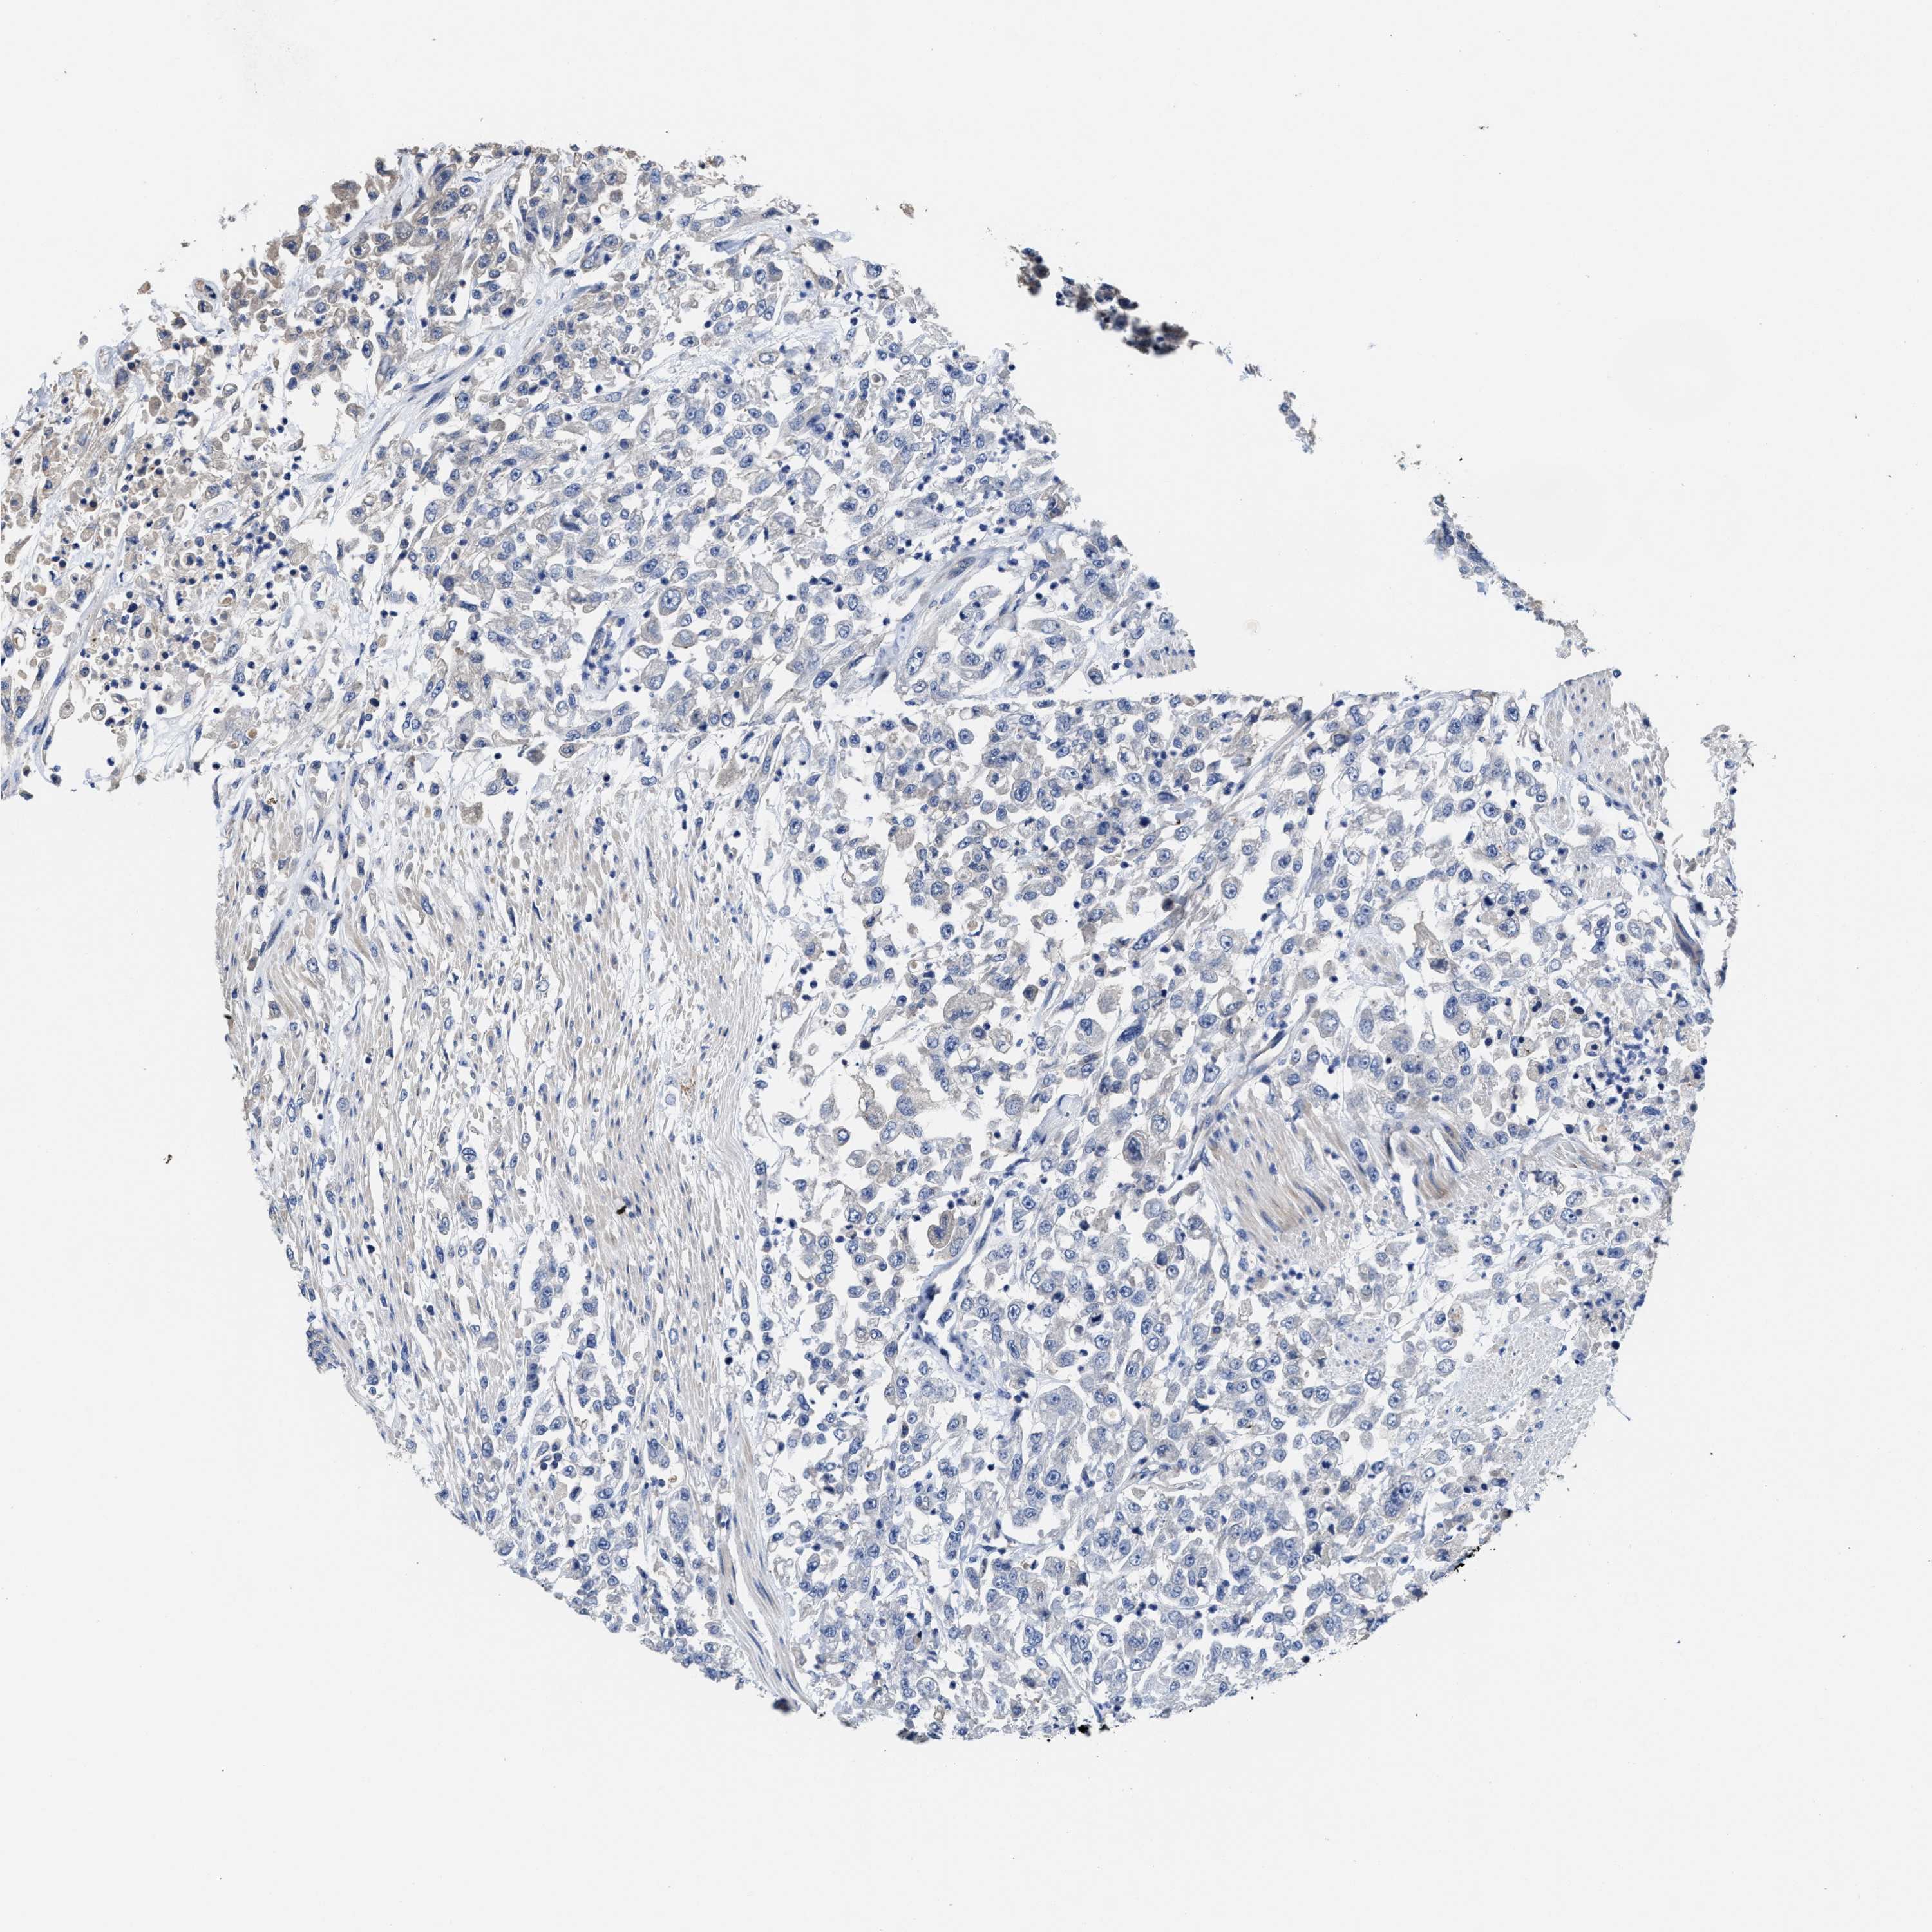

UROTHELIAL CANCER - Protein expressioni

A mouse-over function shows sample information and annotation data. Click on an image to view it in a full screen mode. Samples can be filtered based on level of antibody staining by selecting one or several of the following categories: high, medium, low and not detected. The assay and annotation is described here.

Note that samples used for immunohistochemistry by the Human Protein Atlas do not correspond to samples in the TCGA dataset.

Antibody stainingi

Antibody staining in the annotated cell types in the current human tissue is reported as not detected, low, medium, or high, based on conventional immunohistochemistry profiling in selected tissues. This score is based on the combination of the staining intensity and fraction of stained cells.

Each image is clickable and will lead to virtual microscopy that enables deeper exploration of all samples and also displays staining intensity scores, fraction scores and subcellular localization as well as patient and tissue information for each sample.

Antibody HPA019805

Antibody HPA020599

Antibody CAB004605

Staining

High

Medium

Low

Not detected

Intensity

Strong

Moderate

Weak

Negative

Quantity

>75%

75%-25%

<25%

None

Location

Nuclear

Cytoplasmic/membranous

Cytoplasmic/membranous,nuclear

Urothelial carcinoma, Low grade

Urothelial carcinoma, High grade